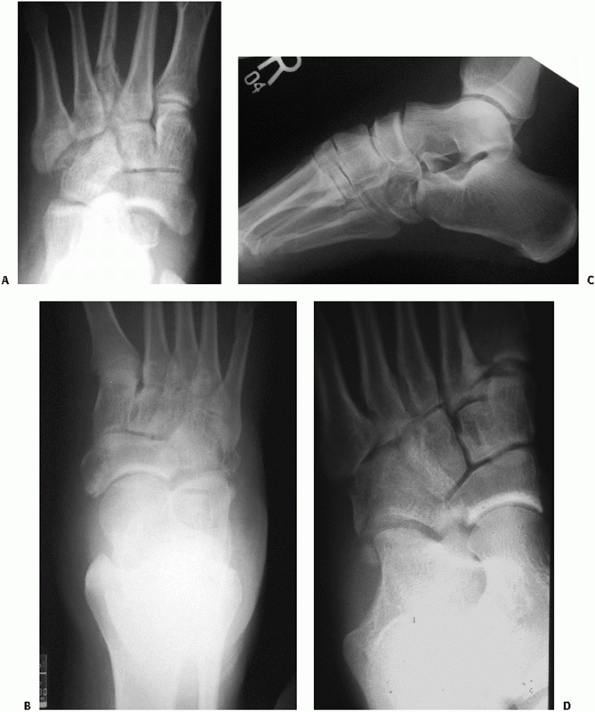

![]() |

FIGURE 60-11 Neuropathic dislocation of the navicular. A. Anteroposterior radiograph with medial deviation of the navicular. B. Lateral radiograph showing plantar migration. C,D. Fixation post reduction for fusion of the naviculocuneiform joints.

FIGURE 60-12 Cuboid fracture patterns. A.

Oblique foot radiograph with cuboid impaction fracture at the tarsometatarsal joint. There is also an associated third metatarsal fracture. B,C. Anteroposterior and lateral radiograph of cuboid with calcaneal cuboid impaction. D. Oblique radiograph of cuboid crush with both calcaneal and metatarsal joint involvement. |